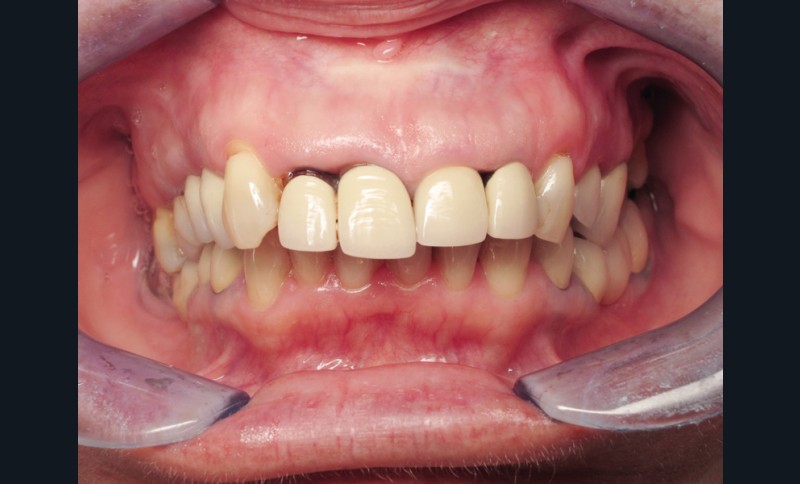

Madame J., âgée de 63 ans, consulte pour des douleurs chroniques localisées au niveau de 14 et de 21. L’examen endobuccal révèle la présence de prothèses anciennes, de soins conservateurs et d’un implant posé depuis 4 ans. On note une inflammation généralisée du parodonte superficiel avec présence de plaque et de tartre et une mobilité de certaines dents dont les incisives maxillaires droites. Dès ce stade, le surguidage antérieur du couple 11/12, reconstitué par des couronnes solidarisées, est à mettre en relation avec la souffrance parodontale observée (fig. 1).

Une inflammation de la zone péri-implantaire (24), en relation avec le motif de la consultation est également visible dès ce premier examen.